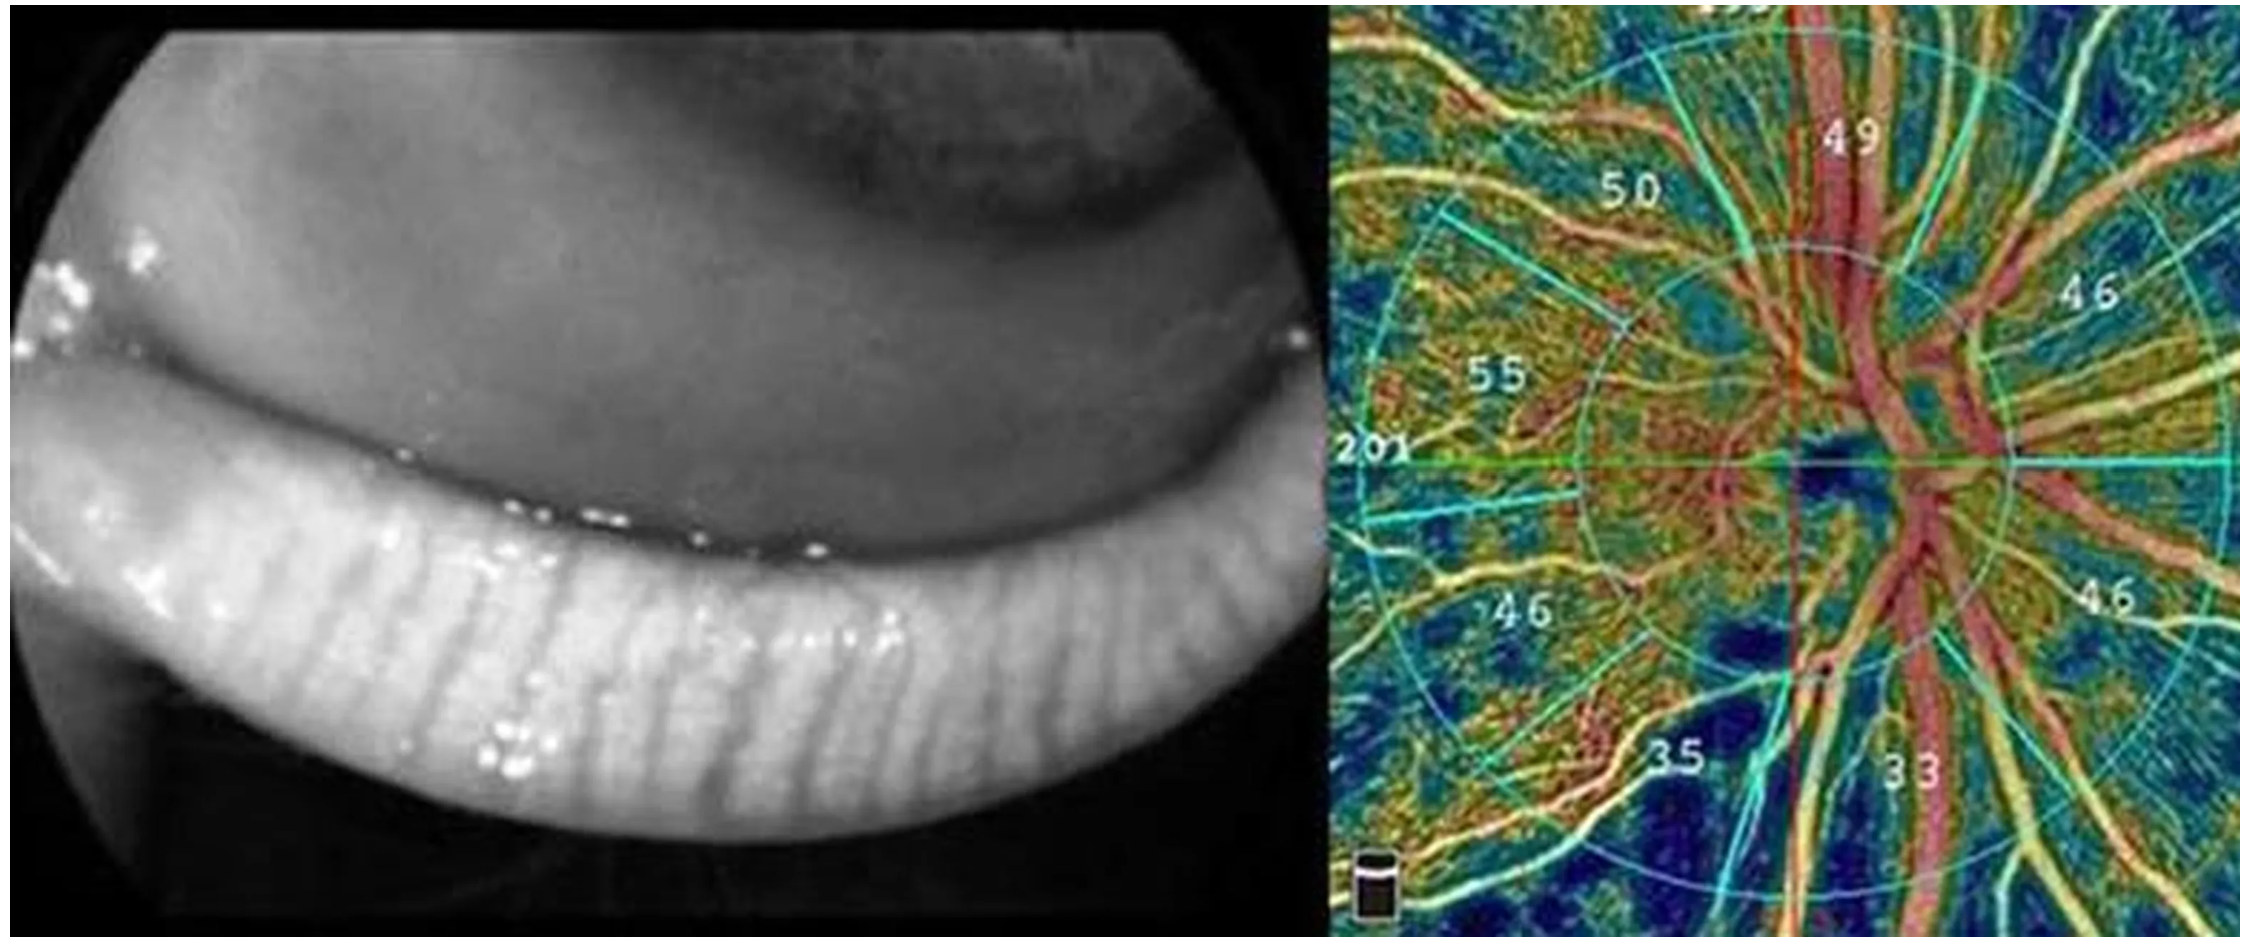

Оптический когерентный томограф Optovue Solix обладает повышенной скоростью сканирования — 120 000 А-сканов в секунду. SOLIX предоставляет множество инструментов для нового поколения борьбы с заболеваниями, которые повышают пропускную способность и обеспечивают превосходный уход за пациентами. В отличие от томографов более ранних поколений ОКТ SOLIX OPTOVUЕ может определять наличие конкрементов и новообразований сосудов сетчатки и хориоидеи, позволяет получать максимально точную послойную визуализацию структур глаза.

- Диапазон сканирования в режиме ангио-ОКТ — от 3х3 до 18х18 мм;

- Программа AngioAnaliticsTM для количественного анализа сосудов сетчатки;

- Оптическая пахиметрия, картирование эпителия и стромы роговицы в зоне диаметром 10 мм.